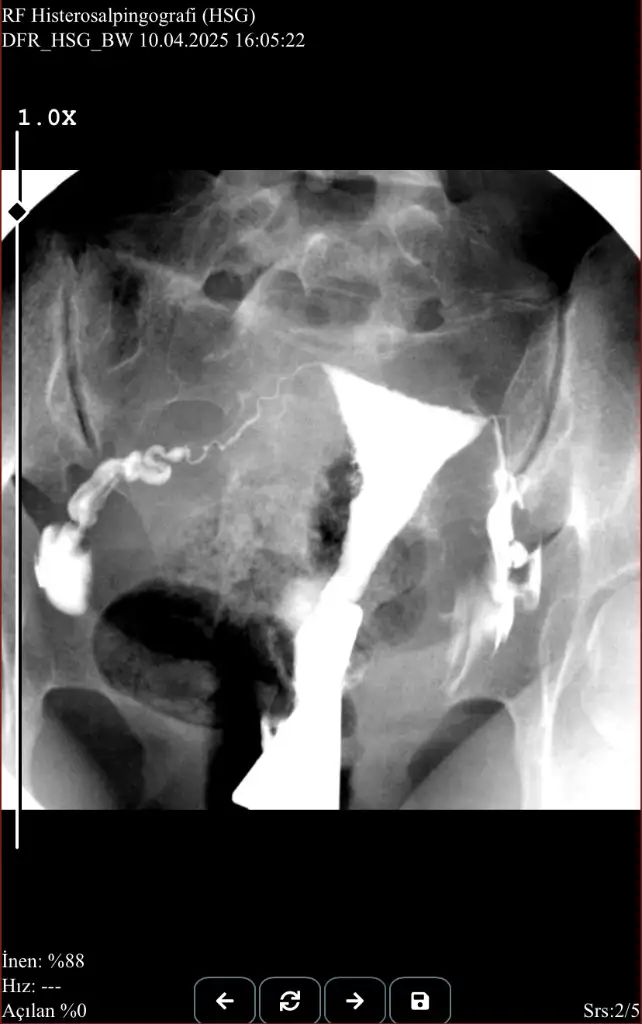

Rahim filmi sonucum da bu şekilde sanırım normal görünüyor.

Yani yine hiçbir sonuca ulaşamadık bu kadar kötü tecrübe hâlâ sadece şanssızlık gibi duruyor..